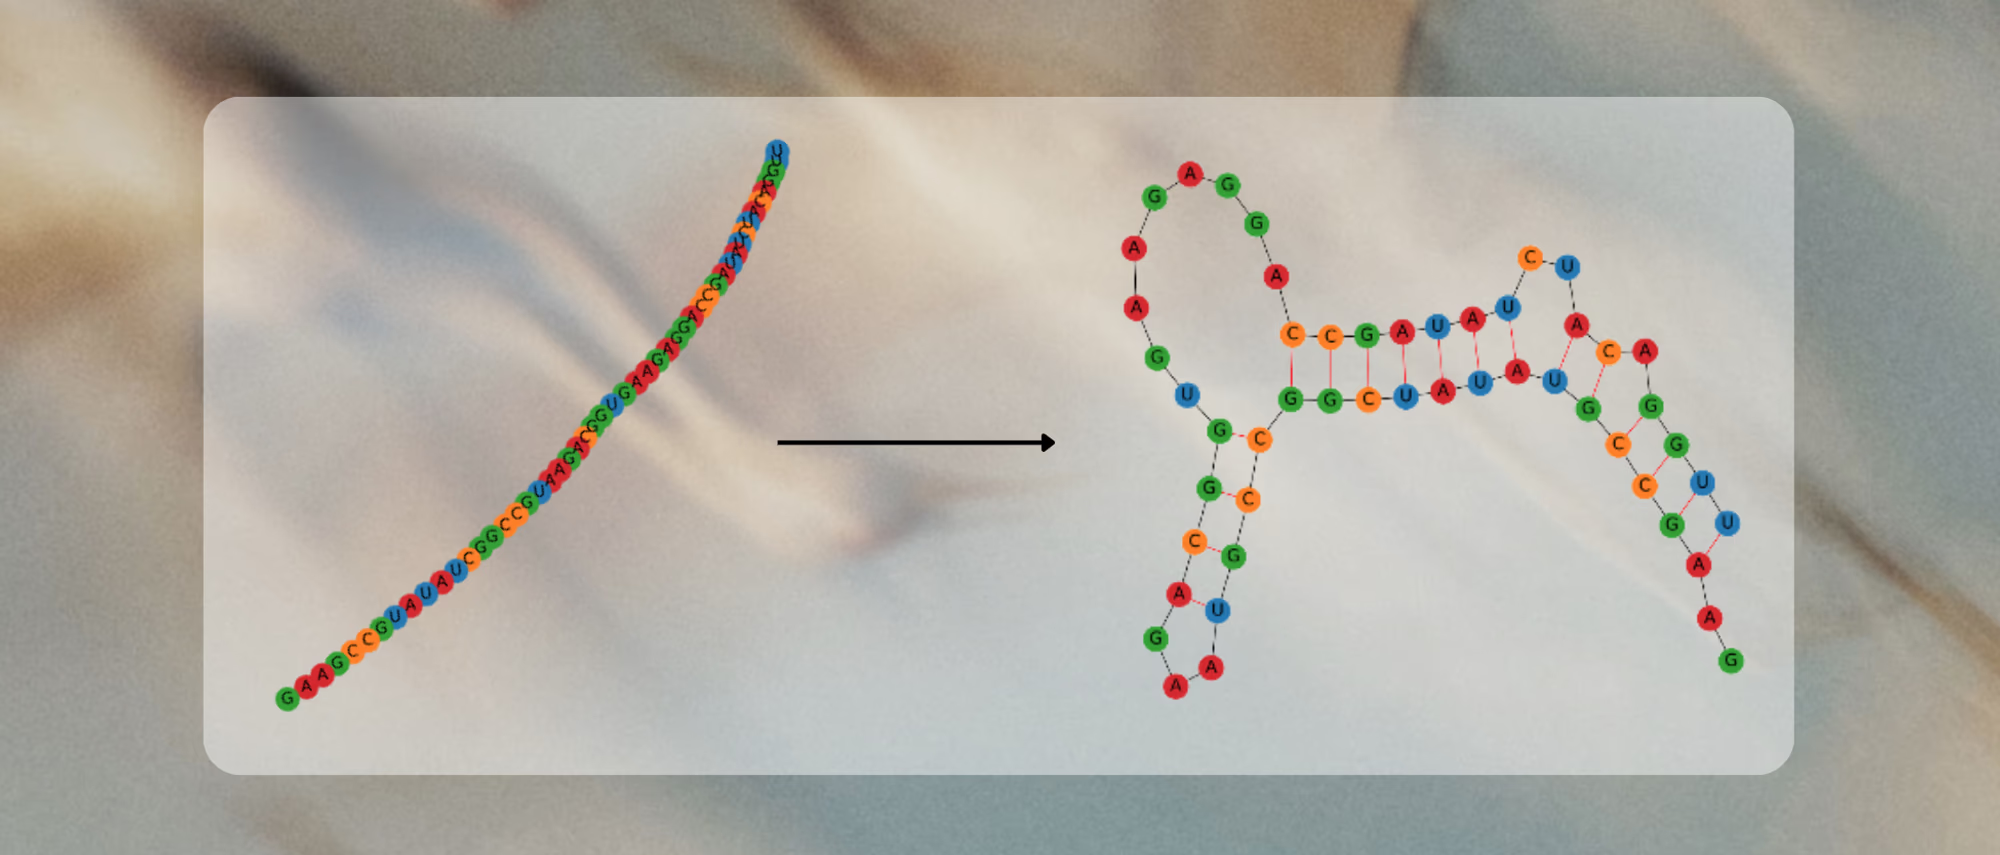

With R&D costs exceeding $2B per drug, pharma increasingly combines machine learning and computational chemistry to accelerate discovery. A powerful approach uses first-principles calculations to generate “quantum fingerprints”—physically grounded features that improve reactivity prediction. However, classical simulation methods scale poorly: they rely on approximations that are either too inaccurate to capture critical many-body effects or too expensive for practical screening.

- Generate predictive quantum features unavailable to classical methods